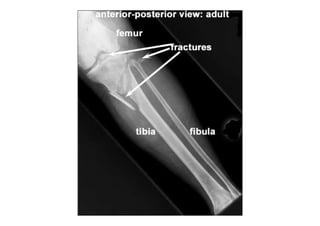

RADIOLOGIA DO

TRAUMA DO ESQUELETO

Referência: http://www.accessexcellence.org/RC/VL/